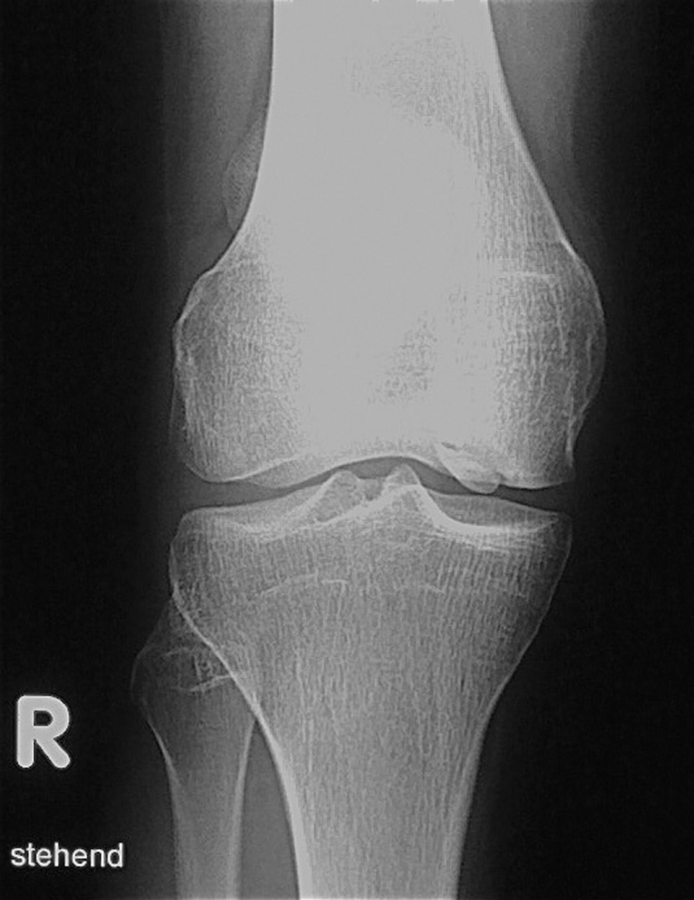

Eine Fraktur? Weit gefehlt. Bei einer Patella bipartita verschmelzen die Ossifikationskerne nicht. Eine Fraktur? Weit gefehlt. Bei einer Patella bipartita verschmelzen die Ossifikationskerne nicht. © wikimedia/Hellerhoff